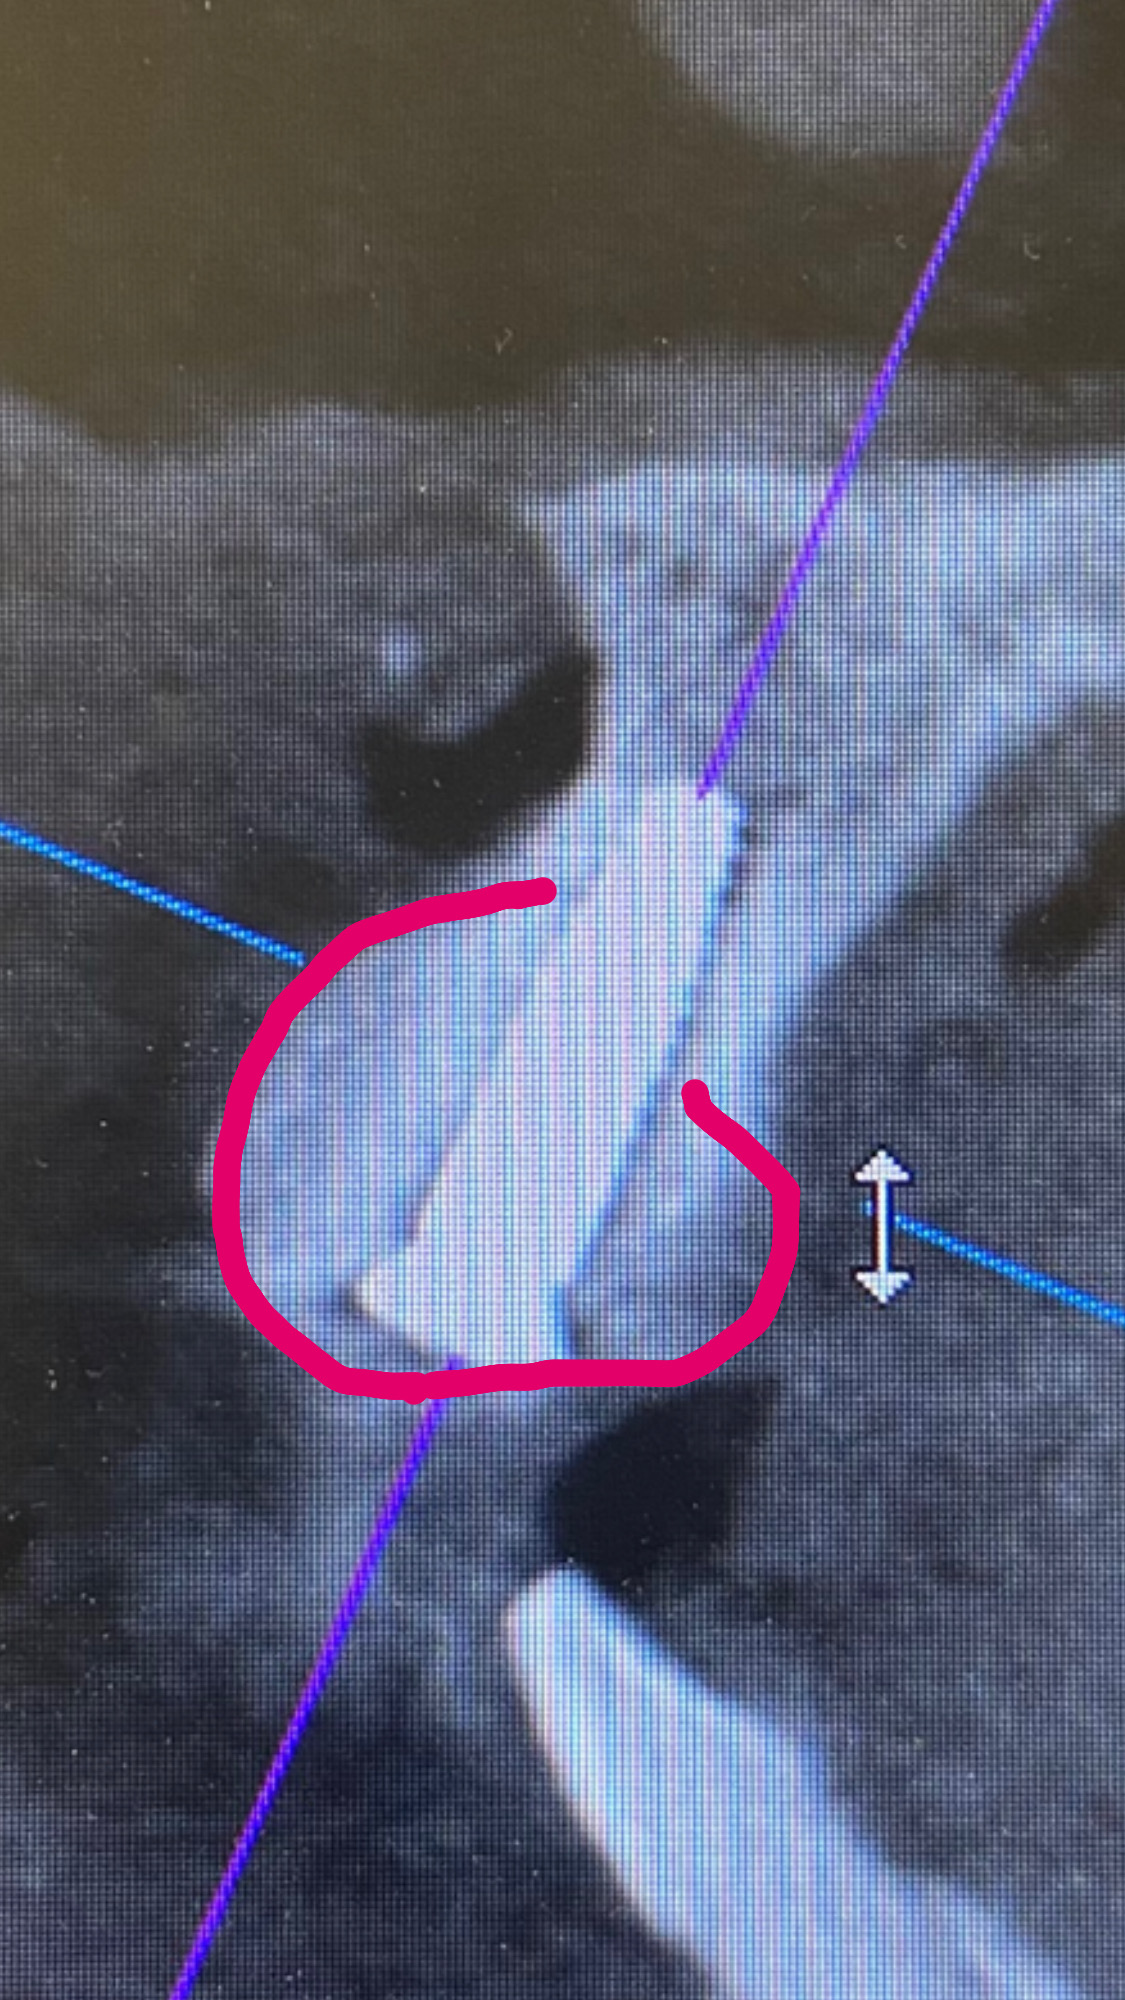

インプラント埋入と同時に骨造成を行ったCTです。

ピンクで囲まれた範囲が人工骨で、人工骨がバラバラにならないように、コラーゲン膜とチタンピンで固定しています。

こけて折れた前歯を長期間そのままにしていたため、炎症により周りの骨が広範囲で無くなっていました。

そのまま骨を増やさずにインプラントを行っても、インプラント自体の持ちも悪く、見た目も悪くなってしまいます。

そのため最終的な被せ物の位置やサイズから逆算し、審美的にベストな位置にインプラントを埋入し骨造成しています。